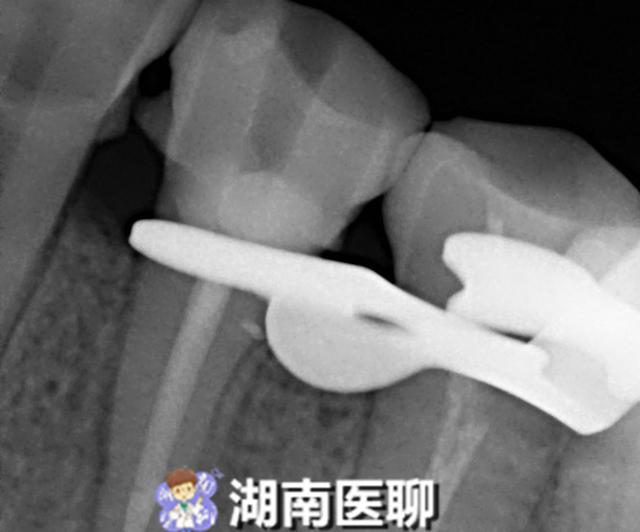

通过进一步详细询问病史、口腔检查及拍摄小牙片后,医生诊断为牙面上深达髓腔的深楔状缺损引发牙齿慢性根尖周炎,引起牙龈冒出脓包。

医生认为要想消除脓包,就要对牙进行根管治疗,消除炎症,于是患者接受了根管治疗,根管清理成形 ,补上了牙面上的深楔状缺损。